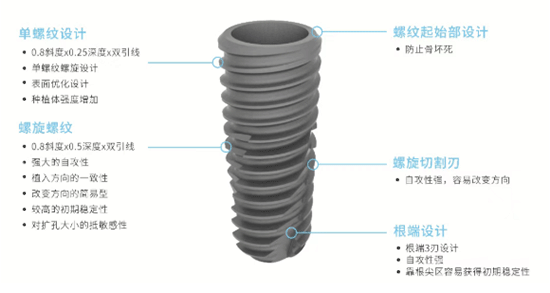

韩国仕诺康种植牙:2180 元 / 颗起

韩国奥齿泰种植牙:3280 元 / 颗起

瑞士 ITI 种植牙:5480 元 / 颗起

国产百康特种植体:3200 元 / 颗起(限时援助价)

韩国登腾种植体:3980 元起

瑞士 SIC 种植系统:6800 元起

美国皓圣种植体:8800 元起

瑞典诺贝尔 Active 种植体:15800 元起

德国贝格 Bego 种植系统:12800 元起,含 3D 导板设计费